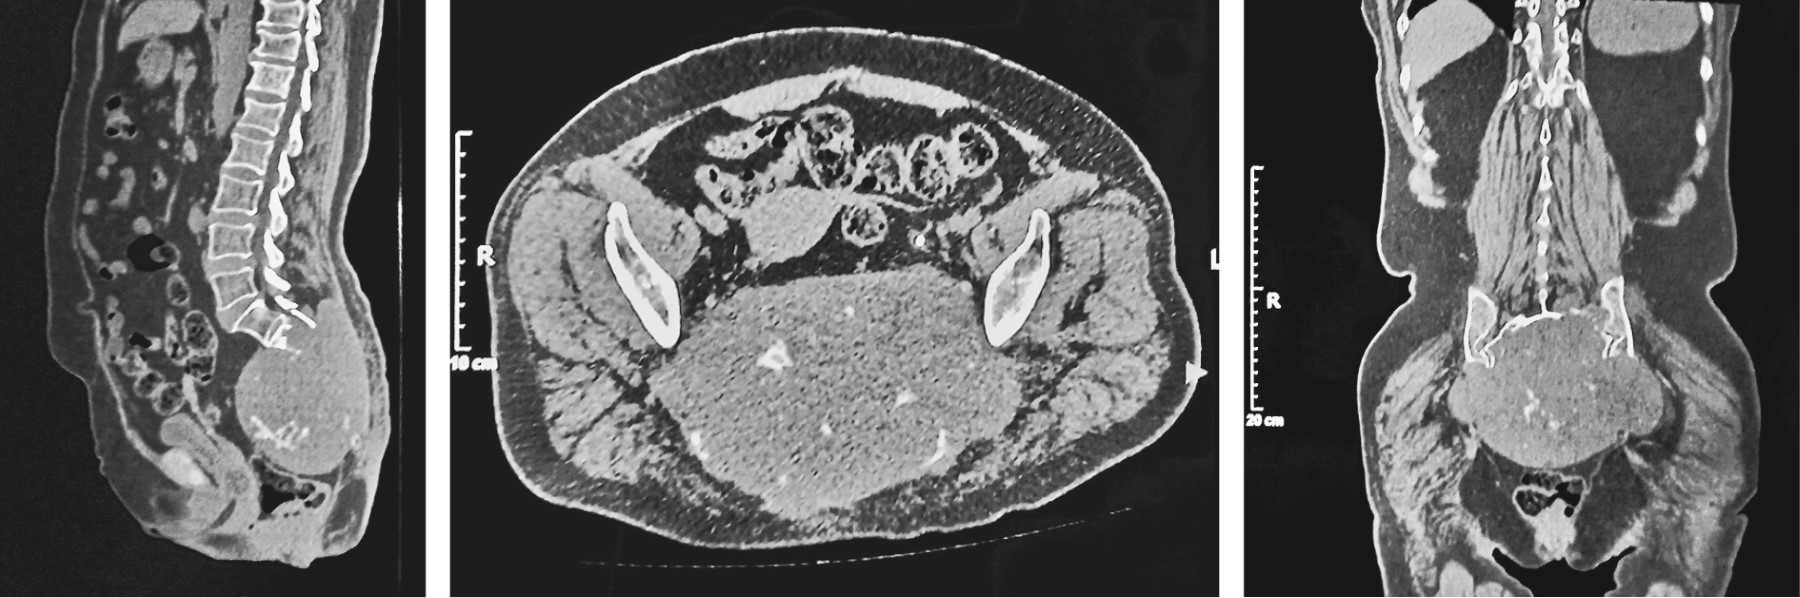

CT is an excellent tool to evaluate cortex integrity, to asses and characterize periosteal new bone formation, and to detect and characterize matrix mineralization; on the other hand, MRI is superior in soft tissue contrast resolution, which provides the ability to sensitively detect lesions, characterize tissue types, and accurately stage tumors locally for their anatomic extent in the bone and soft tissue10 (Figure 3). The combination of T1 and T2 weighted imaging is suitable for evaluating nerve root, muscle and visceral structure involvement.

The CT and MRI scans are necessary tools in the diagnostic process of a sacral mass and very helpful in the preoperative planning, as well as in postoperative period.2,9

Figure 3